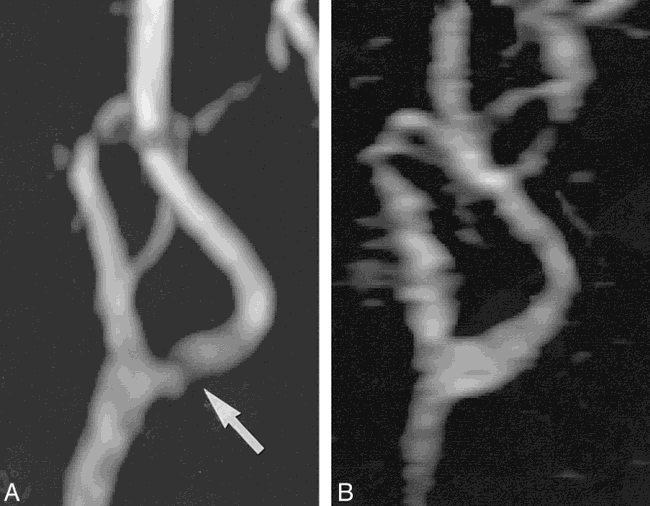

Compared with 2D TOF MR angiography, the severity of the stenosis was less on the rotated targeted MIP projections generated from the contrast-bolus–tracking 3D MR angiographic technique in three carotid bifurcations (one mild and two moderate). In the remaining three, the severity of the stenosis was the same. In one patient, there was an apparent artifactual narrowing at the carotid bifurcation on the 2D TOF MR angiogram. On the contrast-bolus–tracking 3D MR angiogram, the same carotid bifurcation appeared normal (Fig 4).

A, MIP projection of the left carotid bifurcation acquired from a female patient with suspected moderate narrowing (arrow) using 2D TOF MR angiography (TR/TE = 22/7, flip angle = 60°).

B, The MIP projection acquired using subtracted 3D dynamic keyhole turbo field-echo MR angiography (TR/TE = 6/3, flip angle = 50°) shows a patent left carotid bifurcation.

Like other contrast-enhanced MR angiographic techniques, 3D dynamic keyhole turbo field-echo MR angiography seems to be less sensitive to TOF-related artifacts (Fig 4). This is partially because contrast-enhanced MR angiography is less dependent than TOF MR imaging on the inflow of unsaturated spins for the production of the angiographic contrast.